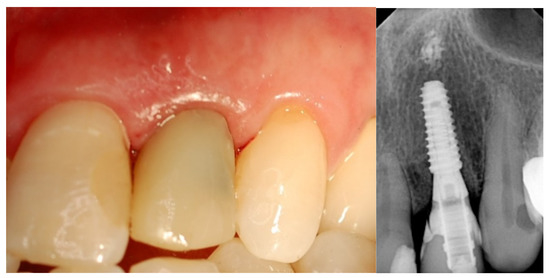

- Esthetic evaluation of clinical pictures, including at least two adjacent teeth, taken at two years after loading was done following the pink esthetic score (PES) proposed by Fürhauser et al., in 2005 [31]. In brief, the PES score evaluates seven variables: mesial papilla, distal papilla, soft tissue level, soft tissue contour, alveolar process deficiencies, soft tissue color and texture. A 0-1-2 scoring system was used, with a maximum achievable score of 14 per site.

| PES 3 at the 2-year follow-up | 12.6 ± 0.97 | 12.2 ± 0.92 | 0.3554 |

| MBL4 at the 2-year follow-up | 0.23 ± 0.11 | 0.18 ± 0.12 | 0.3339 |